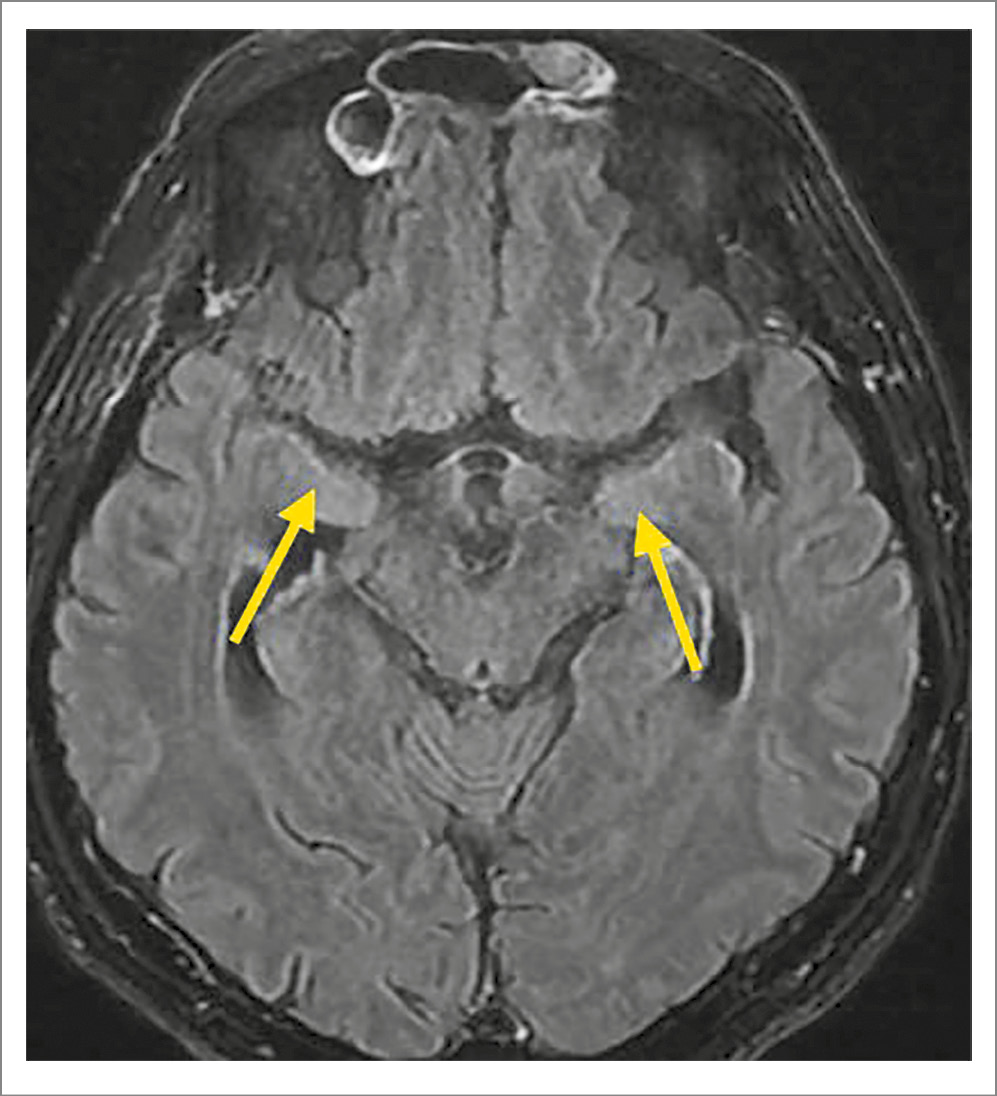

Для исключения патологии головного мозга выполнено МР-исследование суб- и супратенториальных структур головного мозга в Т1- и Т2-взвешенных изображениях, режимах IR-, FLAIR- и DWI в сагиттальной, коронарной и аксиальной проекциях с контрастированием. Срединные структуры не смещены, III и IV желудочки не расширены. В медиальных отделах височных долей, более выраженно в левой, в Т2-FLAIR-режиме в аксиальной проекции определяются участки слабо гиперинтенсивного измененного МР-сигнала без четких границ. В белом веществе обоих полушарий, лобно-теменных отделах определяются немногочисленные перивентрикулярные очаги гиперинтенсивного сигнала на Т2 в режиме FLAIR с нечеткими контурами до 6 мм.

Заключение: МР-картина изменений в медиальных отделах височных долей соответствует ЛЭ, необходимо исключить паранеопластическую природу (рис. 1).

Рис. 1. Пациент Б., 56 лет. МРТ головного мозга с контрастированием. Т2-FLAIR – аксиальный срез. Определяется гиперинтенсивный МР-сигнал от медиальных отделов височных долей (желтая стрелка).

По данным МРТ головного мозга в представленном случае в медиальных отделах височных долей с большей выраженностью слева в режиме T2-FLAR определяется гиперинтенсивность МР-сигнала.